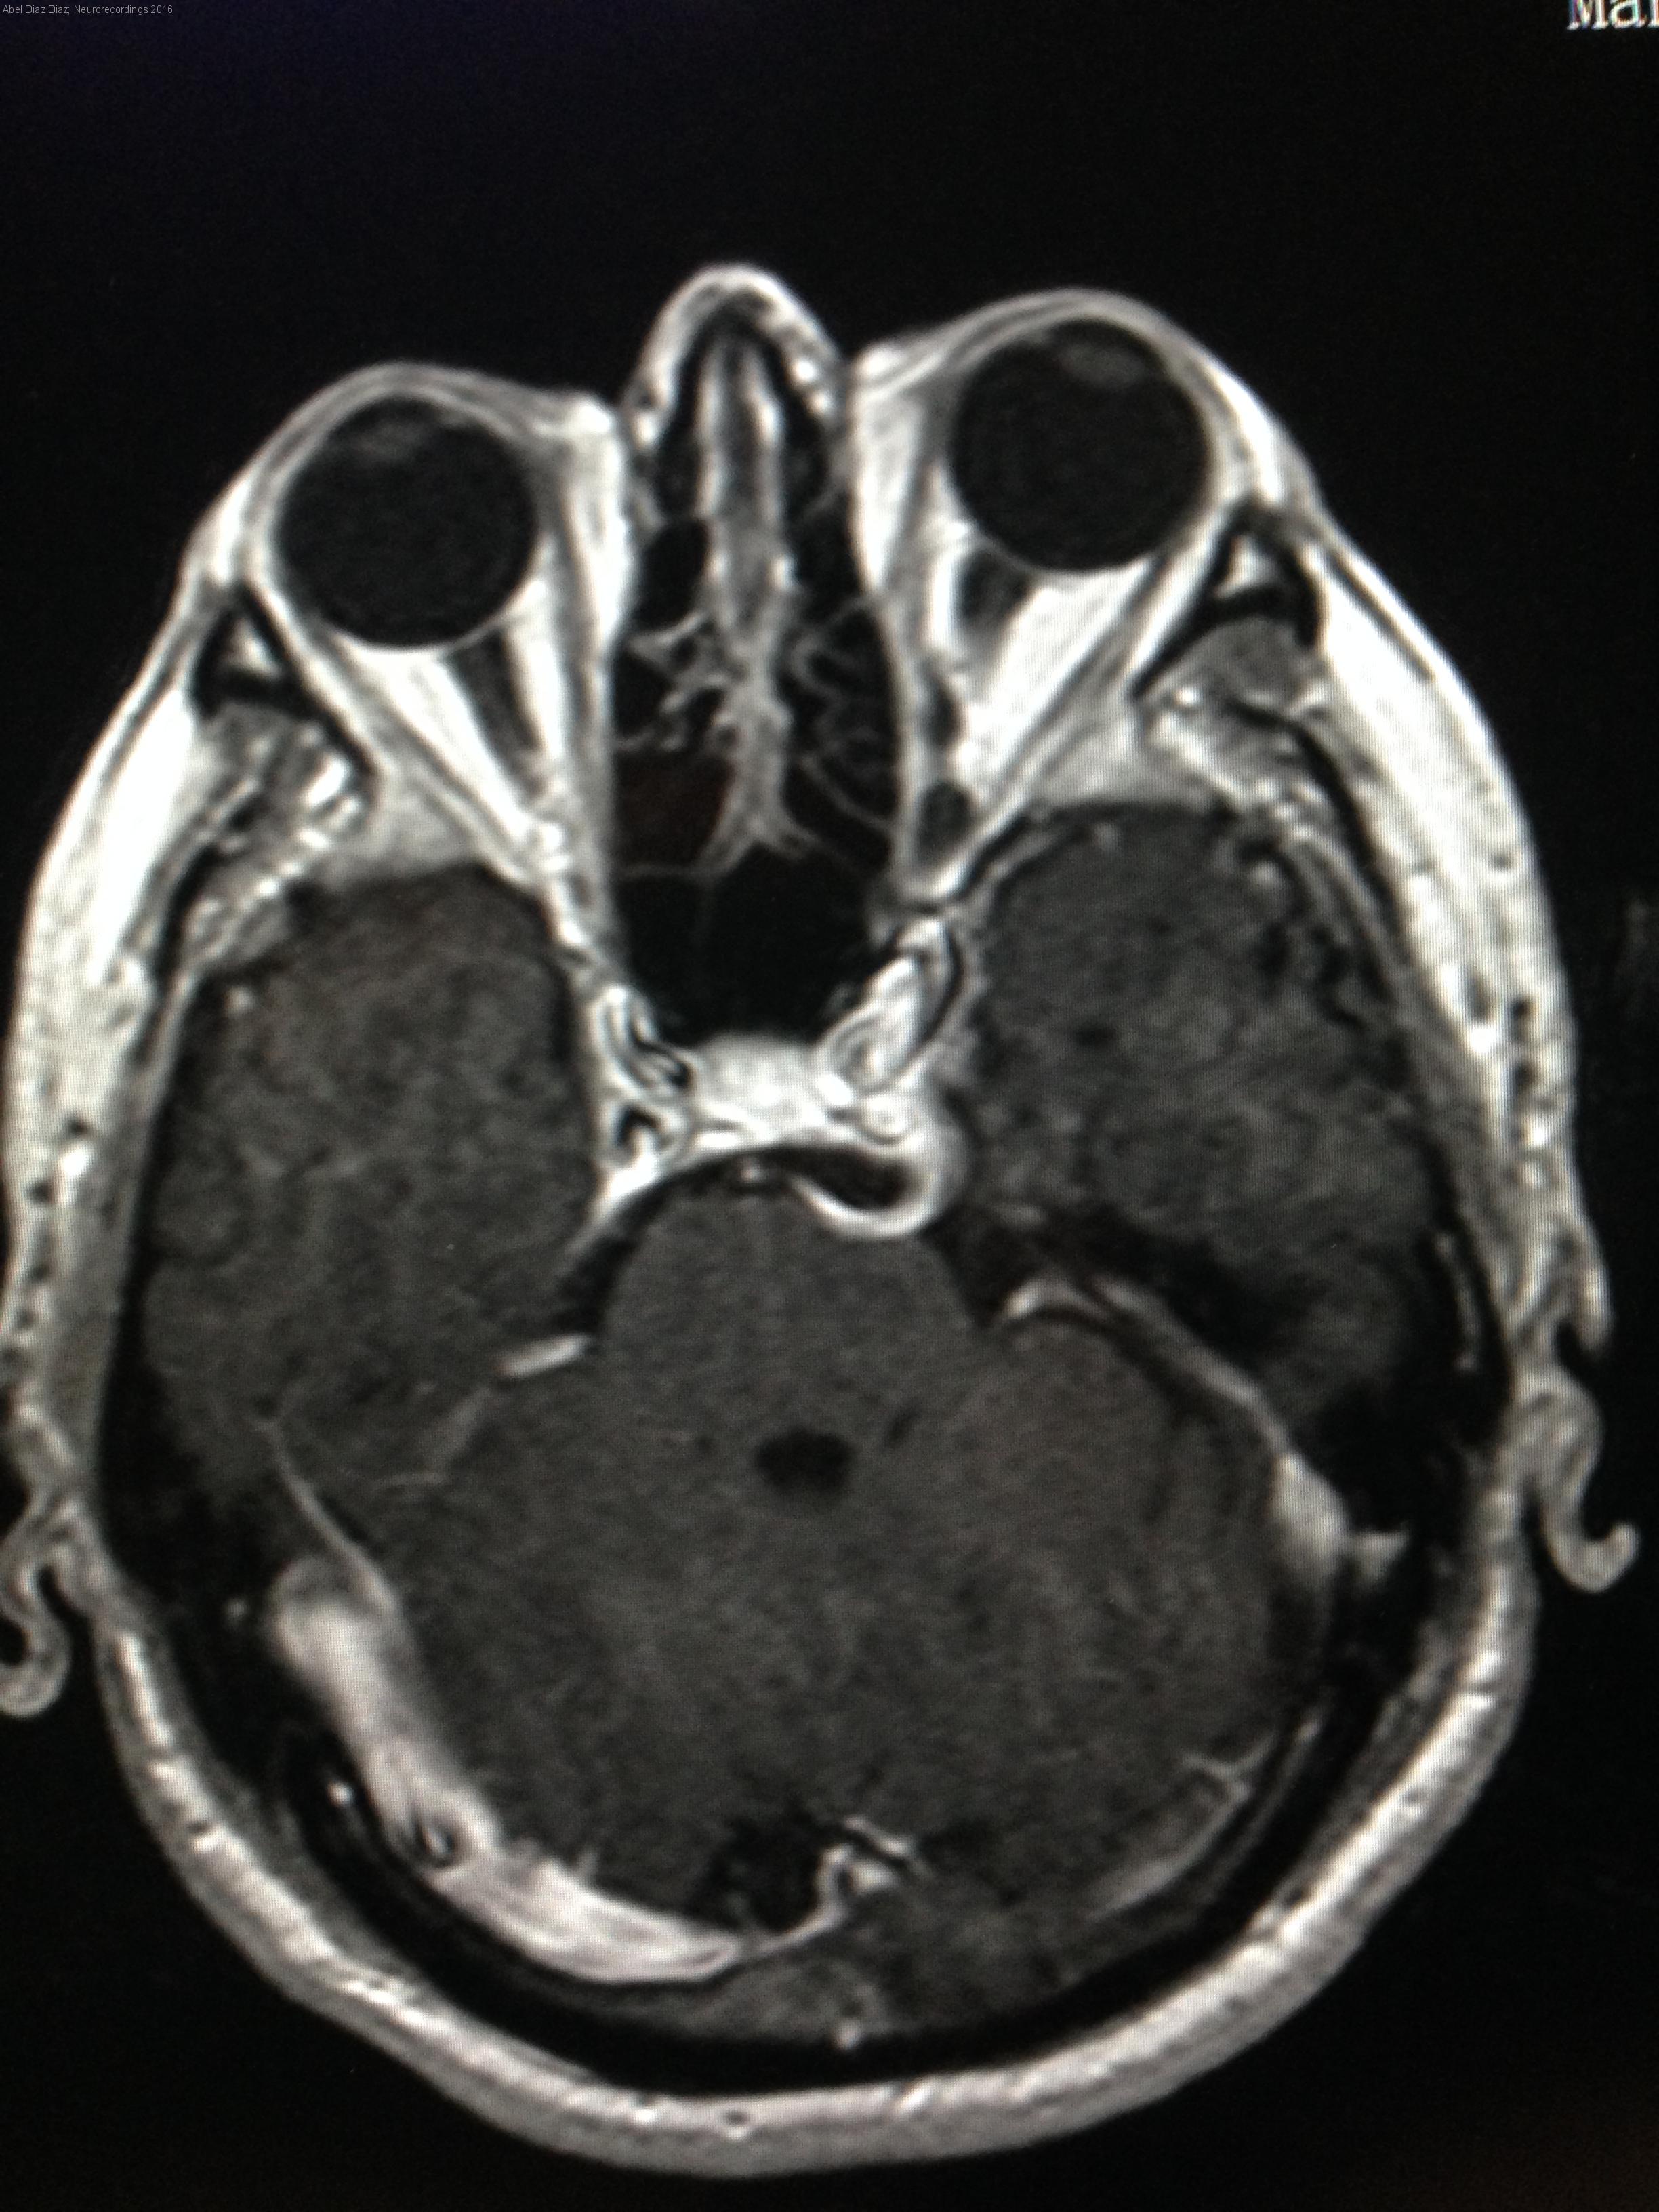

Hombre | 60 años

Diagnóstico final: Arteria trigeminal persistente

Varón de 60 años que consulta por visión doble horizontal con la mirada lejana de meses de evolución. A la exploración física se objetiva proptosis de ojo izquierdo y paresia de sexto par izquierdo. Se solicita TAC...